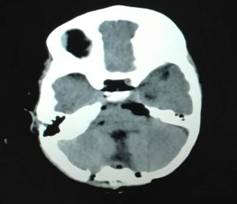

近日,郑州大学五附院神经外科二病区收治了一名因第四脑室肿瘤引起急性脑积水1岁患儿,入院时表现为频繁呕吐、精神萎靡,神经外科二病区吴建珩副主任医师带领的诊疗组接诊后考虑患儿为肿瘤堵塞脑脊液循环通路,造成梗阻性脑积水及颅内压增高,时间就是生命,来不及常规行MRI检查,急诊行增强CT检查,CT检查结果回示患者小脑蚓部巨大肿瘤充满第四脑室,大小约30mm×30mm×35mm,考虑室管膜瘤,脑积水严重,脑疝风险极高,生命危在旦夕。患儿才刚满1岁不久,正是父母的心头的宝,若是遭此不幸,毫无疑问对其父母以及整个家庭都是难以承受的巨大的打击。

术前:肿瘤组织巨大